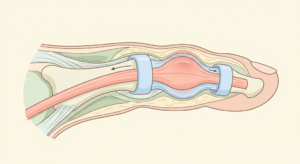

テニス肘の直接的な原因は、手首を反らす動作(伸筋)の使いすぎです。特に「短橈側手根伸筋(たんとうそくしゅこんしんきん)」という筋肉の付け根に微細な断裂が生じることで痛みが起きます。